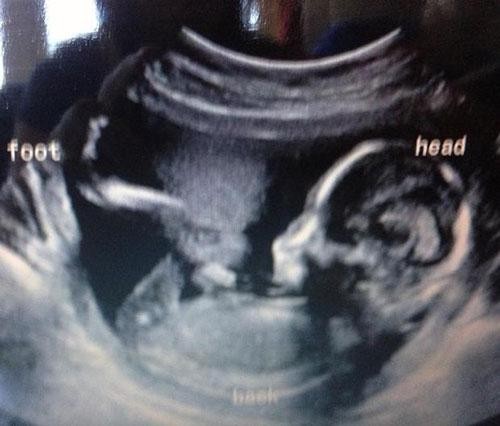

Kuş